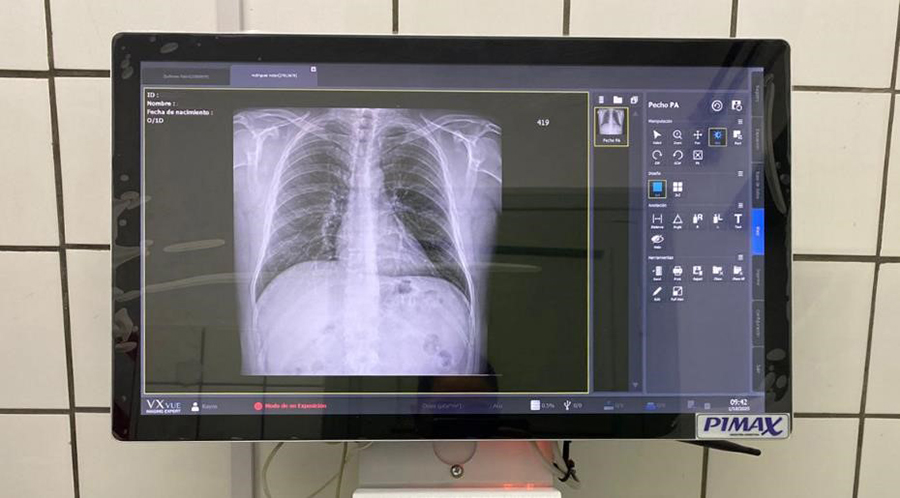

En septiembre, la II Brigada Aérea adquirió un Sistema Digital para el Servicio de Radiografías del Escuadrón Sanidad de la Unidad. Dicho equipamiento está compuesto por un Flat Panel marca VIEWORKS Modelo 1717VA, PC All in One con WIN10 PRO, incluyendo teclado, mouse y mobiliario específico para el correcto funcionamiento de dicho Sistema.

El Sistema de Digitalización actualiza y agiliza la acción del revelado y pone en un nivel superior a nuestro Servicio de Radiografías, mejorando así la calidad de imagen para posteriores diagnósticos tanto en psicofísicos como en consultorio y en urgencias, con eficiencia y eficacia.